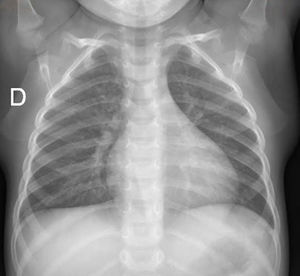

A las 24h permanece asintomático, con resolución completa de la atelectasia (fig. 3), por lo que se decide alta a domicilio con tratamiento antiasmático, sin presentar recidivas.